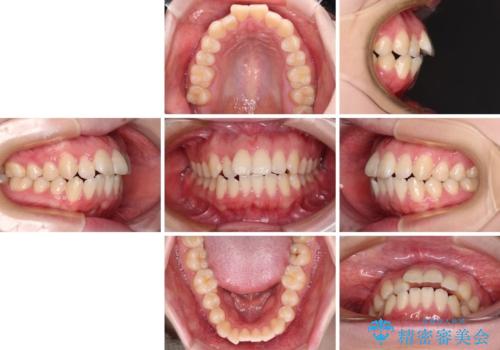

- 上顎前歯が前方に飛び出していることを気にして来院された患者様です。

強い舌の突出癖により、上下前歯が前方に飛び出しており、特に上顎前歯は下顎よりも更に前方に位置している状態でした。

上顎前歯をしっかりと後方に移動させるため、口蓋側にアンカースクリューと補助装置を併用し、上下左右の第一小臼歯4本を抜歯し、ワイヤー装置にて矯正治療を行うこととしました。

また、舌のトレーニングをしっかりと行うことで、突出癖改善を試みることとしました。